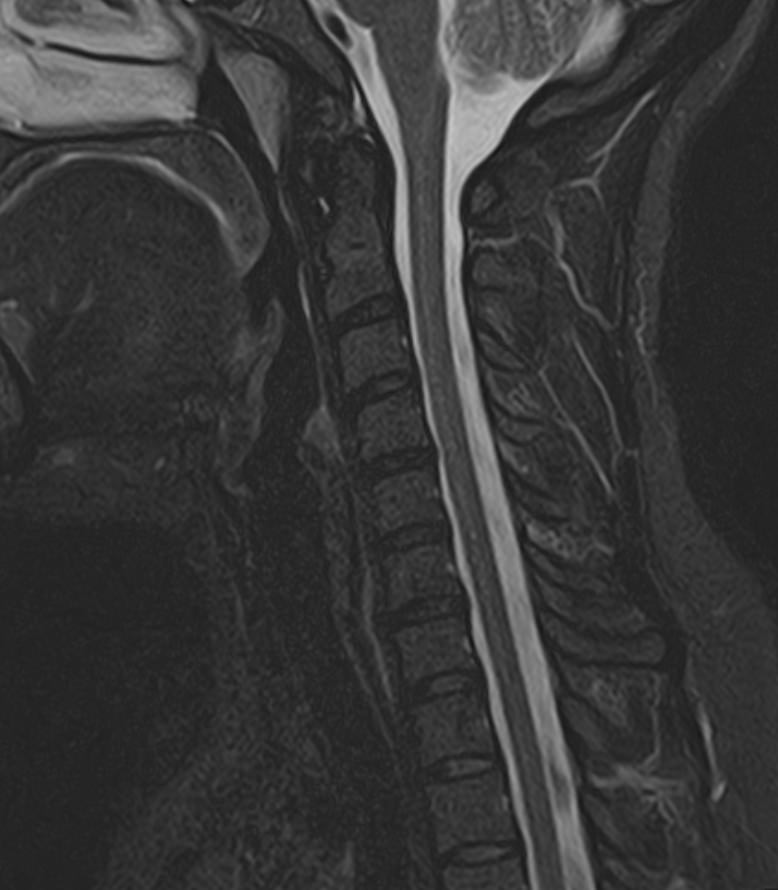

Шейный отдел позвоночника — это самый подвижный сегмент позвоночного столба, который испытывает повышенные нагрузки, подвержен травмам и развитию различных заболеваний. В эту анатомическую область входит 7 верхних позвонков, спинной мозг с отходящими от него нервными корешками.

Сканирование проводится на современном высокопольном магнитно-резонансном томографе закрытого типа TOSHIBA VANTAGE TITAN 1,5 Тесла. Магнитно-резонансный томограф производит послойное сканирование исследуемой зоны в разных плоскостях, затем при помощи компьютерных программ преобразует полученные данные в трехмерные изображения. При этом кровеносная система реконструируется как вместе с окружающими тканями, так и отдельно без них.

• остеохондроз, спондилоартроз, спондилез, межпозвонковые грыжи, унковертебральный артроз, сколиоз, усиленный или выпрямленный лордоз как нарушение статической функции позвоночника, травмы, аномалии позвоночника.